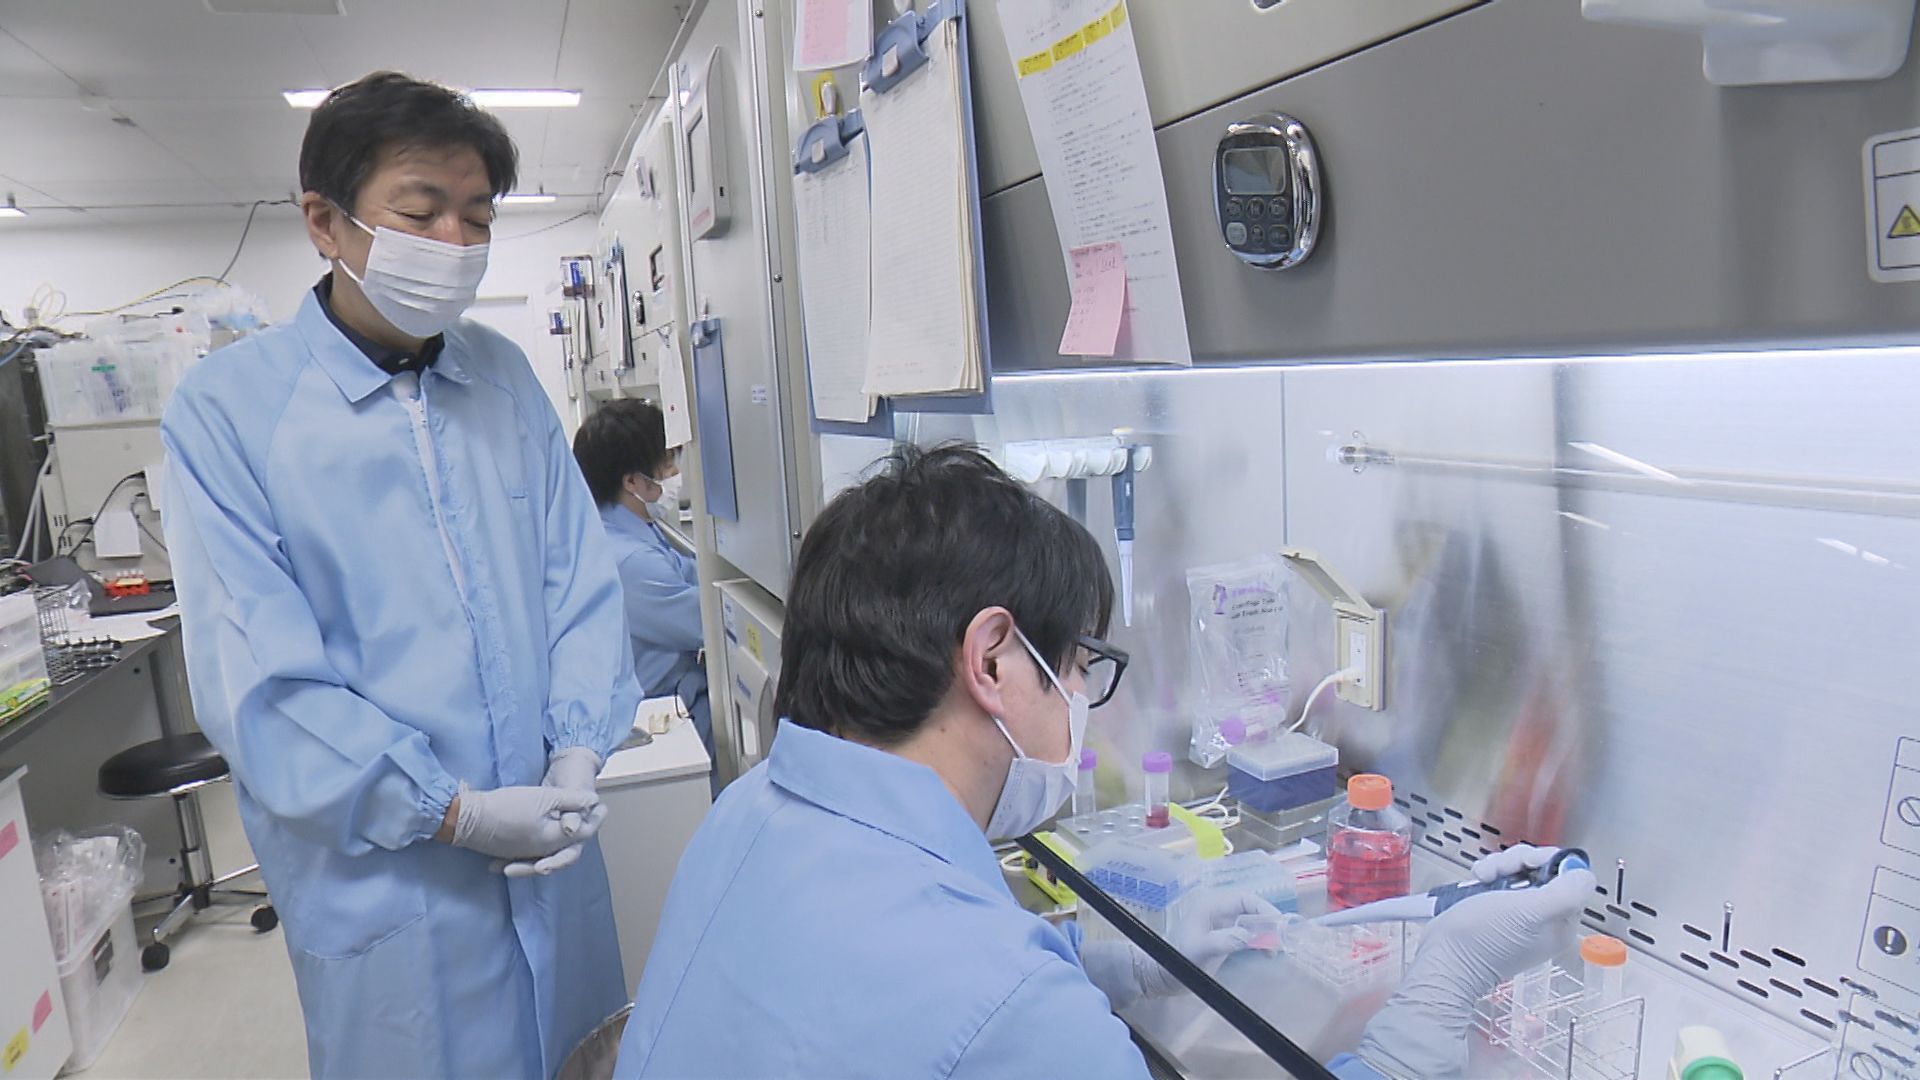

そして、全身の臓器の細胞に分化することができるヒト「iPS細胞」から、心臓の筋肉の細胞「心筋細胞」をつくり、厚さ0.1ミリのシート状に加工した「心筋シート」を開発した。

5年前には、重い心臓病(虚血性心筋症)の患者の心臓に「心筋シート」を貼りつけ移植する手術に世界で初めて成功。

手術はこれまで8例実施されていて、いずれも経過は順調だという。

この心筋シートの技術を応用し、作成されたのが万博の「iPS心臓モデル」だ。

■「立体的な心臓を見せよう」提案した科学者

万博のパソナパビリオンで最先端の心臓治療展示を行うことが決まった際、クオリプスの会議では「心筋シートを一反木綿のように泳がせる」「シートを羽ばたくように見せる」といった案が上がったという。

そこで、「立体的な心臓の形をやりましょう」と提案した科学者がいる。

研究部の長谷川光一部長だ。

【クオリプス・長谷川光一博士】「心筋シートだと『それで心臓なんだよ』と言われても『あっそう』という感じなんです。それが心臓の形をしているとなると、『心臓の細胞で生きているんだ』ということを皆さんに伝えることができるんじゃないかと思ったんです」

2022年、長谷川さんは澤教授に誘われ「クオリプス」の一員となり、現在に至る。

万博開幕の2年前、iPS細胞由来の心筋細胞を使った「立体的な心臓の形」をつくるという、長谷川さんの提案をベースにプロジェクトは始まったが、そう上手くはいかなかった。

■失敗続きの「iPS心臓」開発 流れを変えたマッドサイエンティスト

たくさんの心筋シートを貼り合わせて、心臓の形を目指すもボール状にしかならない。

3Dプリンターを使って心筋細胞の層を重ねてみるなど試行錯誤を繰り返したが失敗続き。

この心臓の形を目指して、長谷川さんと二人三脚で開発に挑んだのが奥田雄一博士だ。

■「ぶら下げた方がいいんです」強く拍動した心臓

万博・開幕のおよそ1年前、長谷川さんと奥田さんの2人は、心臓の形をしたコラーゲンをスポンジ状に加工し、心筋細胞を染み込ませ、人の体温と同じ37℃前後で、外的な刺激を与えなくても自律拍動させるところまで開発を進めていた。

しかし、その心臓を横に寝かせると、目視で拍動がわかるレベルには達しておらず、展示するには程遠い状態だったという。

そこで奥田さんが提案したのが、実際の心臓と同じく、縦にして吊り下げるという手法だった。

iPS心臓モデルにナイロンの細いワイヤ―を通し、培養液の中で吊り下げると、実際の心臓と同じように拍動したのだ。

【クオリプス・長谷川光一博士】「寝かしたままで、鏡を置いて立っているように見せることができればいいという意見もあったんですけど、奥田さんの『いやいや吊ってみましょうよ』っていうアイデアで吊り下げてみたら、平面でいるときよりも、心なしか拍動が自然の形に近いのか、強い感じがしてですね、不思議だなと思って」

「万博が終わったら、何が起こっているのか研究しようと思っているんです。吊り下げると拍動が強くなるので、何かしらのことが起こっていると思うんです」

奥田さんの「心臓を吊り下げる」という発想には、研究を見守っていた澤教授も驚いたという。

【大阪大学・澤芳樹特任教授】「もう突然、開幕の1年ぐらい前に、奥田君が僕に『心臓が動き出しました』って言ってくれたんです。それまでは、ほとんど動いてなかったんですよ。こんなこと技術的にできるわけがないと思っていたら、奥田君が『できた』っていうから、『ほんまか?』って言って。それで、奥田君が『ぶら下げた方がいいです』と」

「糸で吊ることで、動き出すということがわかったので、これも『サイエンス』ですよね。吊らなかったら動かないのに、吊ったら必ず動くんだというところで再現性がある」

「なぜ吊ったら動くかということが大事で、おそらく心筋細胞に与える重力とか、いろんな影響があるのかもしれない。もともと持っている遺伝子じゃなくて、環境因子がそういう影響を与えて、細胞の性格を変えたがために、寝ていたら動かなかったのが、立てたら動くようになるというね」

■開幕直前まで続いた微調整 完成した「iPS心臓モデル」

その後も、長谷川さんと奥田さんは、開幕直前まで、できる限り大きく、そして実際の心臓と同じように強く拍動するiPS心臓の展示を目指して開発を進めた。

しかし、実際の心臓大きさに近づけようと、コラーゲンの型を大きくすると、厚みも増した分、コラーゲンが硬くなり拍動しない。

今度は、大きくしたうえで、拍動を強くするため、コラーゲンの厚みを薄くし、柔らかくすると、染み込んだ心筋細胞の拍動に負けてコラーゲンが破けてしまう。

ちょうどいい硬さで、実際の心臓のように動くモデルを目指した結果、最終的にたどり着いたのが、厚さ0.1ミリ、3.5センチの大きさだった。

2人は、5センチの自律拍動するiPS心臓モデルの開発に成功していたものの、長期間拍動させるには安定性が乏しく、製造コストも膨れ上がることから展示は難しいと判断したという。

■「1個1個が生き物。同じ子はいない」

心筋細胞そのものは、1カ月以上生き続けるものの、「iPS心臓モデル」は製造して1週間後に目視でわかる拍動をはじめ、その後2週間ほどで拍動が鈍くなる。

万博の開催期間中は、目視で拍動がわかるiPS心臓モデルの展示を継続するために、展示用に2つ、予備1つの合計3つの心臓モデルを常に切らなさないようパビリオンに置いている。

【クオリプス・奥田雄一 博士】「一番理想的には強く、長くもってくれるのが一番いいんですけど、やっぱり、いいとこどりにはならないので、めっちゃ元気な子は短命やったりするし、すごく緩やかに息長く拍動したりする子もいるんで」

「どれが一番いいかというのは、その時々の見た目で判断するしかないんですけど、結構個性分かれますね。1個1個がやっぱり生き物なんで、同じ子はいないんですよね」